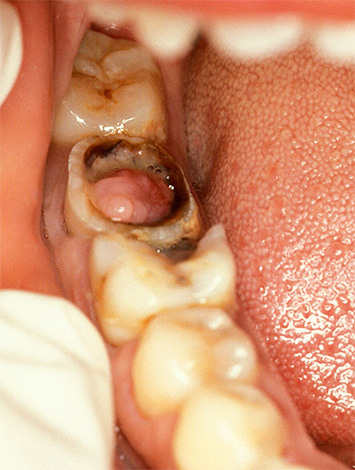

Per quanto riguarda il cronico polpite cancrenosa, quindi forse il sintomo più comune di questa forma di malattia è un odore sgradevole che si diffonde dal dente. Un sintomo frequente è anche il dolore crescente dal caldo, che non si ferma per molto tempo, anche dopo che l'irritante non è più in bocca. A volte ci sono dolori di scoppio nel dente.

Anche se si osserva un decorso asintomatico, molti notano un cambiamento nel colore dei denti: l'aspetto di un colore grigiastro. Di norma, la comparsa di tutti questi sintomi della pulpite gangrenosa cronica è preceduta da dolori acuti e spontanei, che poi scompaiono. Ciò suggerisce che in molte persone il decorso cronico della malattia è preceduto dalla sua forma acuta.

Se c'è un messaggio con una cavità cariata e compaiono dolore e sanguinamento quando si sondano con una sonda acuta, allora con un alto grado di probabilità è cronico pulite fibrosa. Con un cambiamento nel colore dei denti, l'aspetto di un'ombra grigia, con una grande quantità di tessuto cariato ammorbidito nella cavità del dente, quando il "nervo" viene parzialmente distrutto e il dolore si verifica solo quando si sondano i canali, allora è molto probabilmente una polpite cranica cronica. La comparsa di tessuto troppo cresciuto all'interno della cavità in combinazione con l'indolenzimento quando lo sondano il più delle volte indica una polpite ipertrofica cronica.